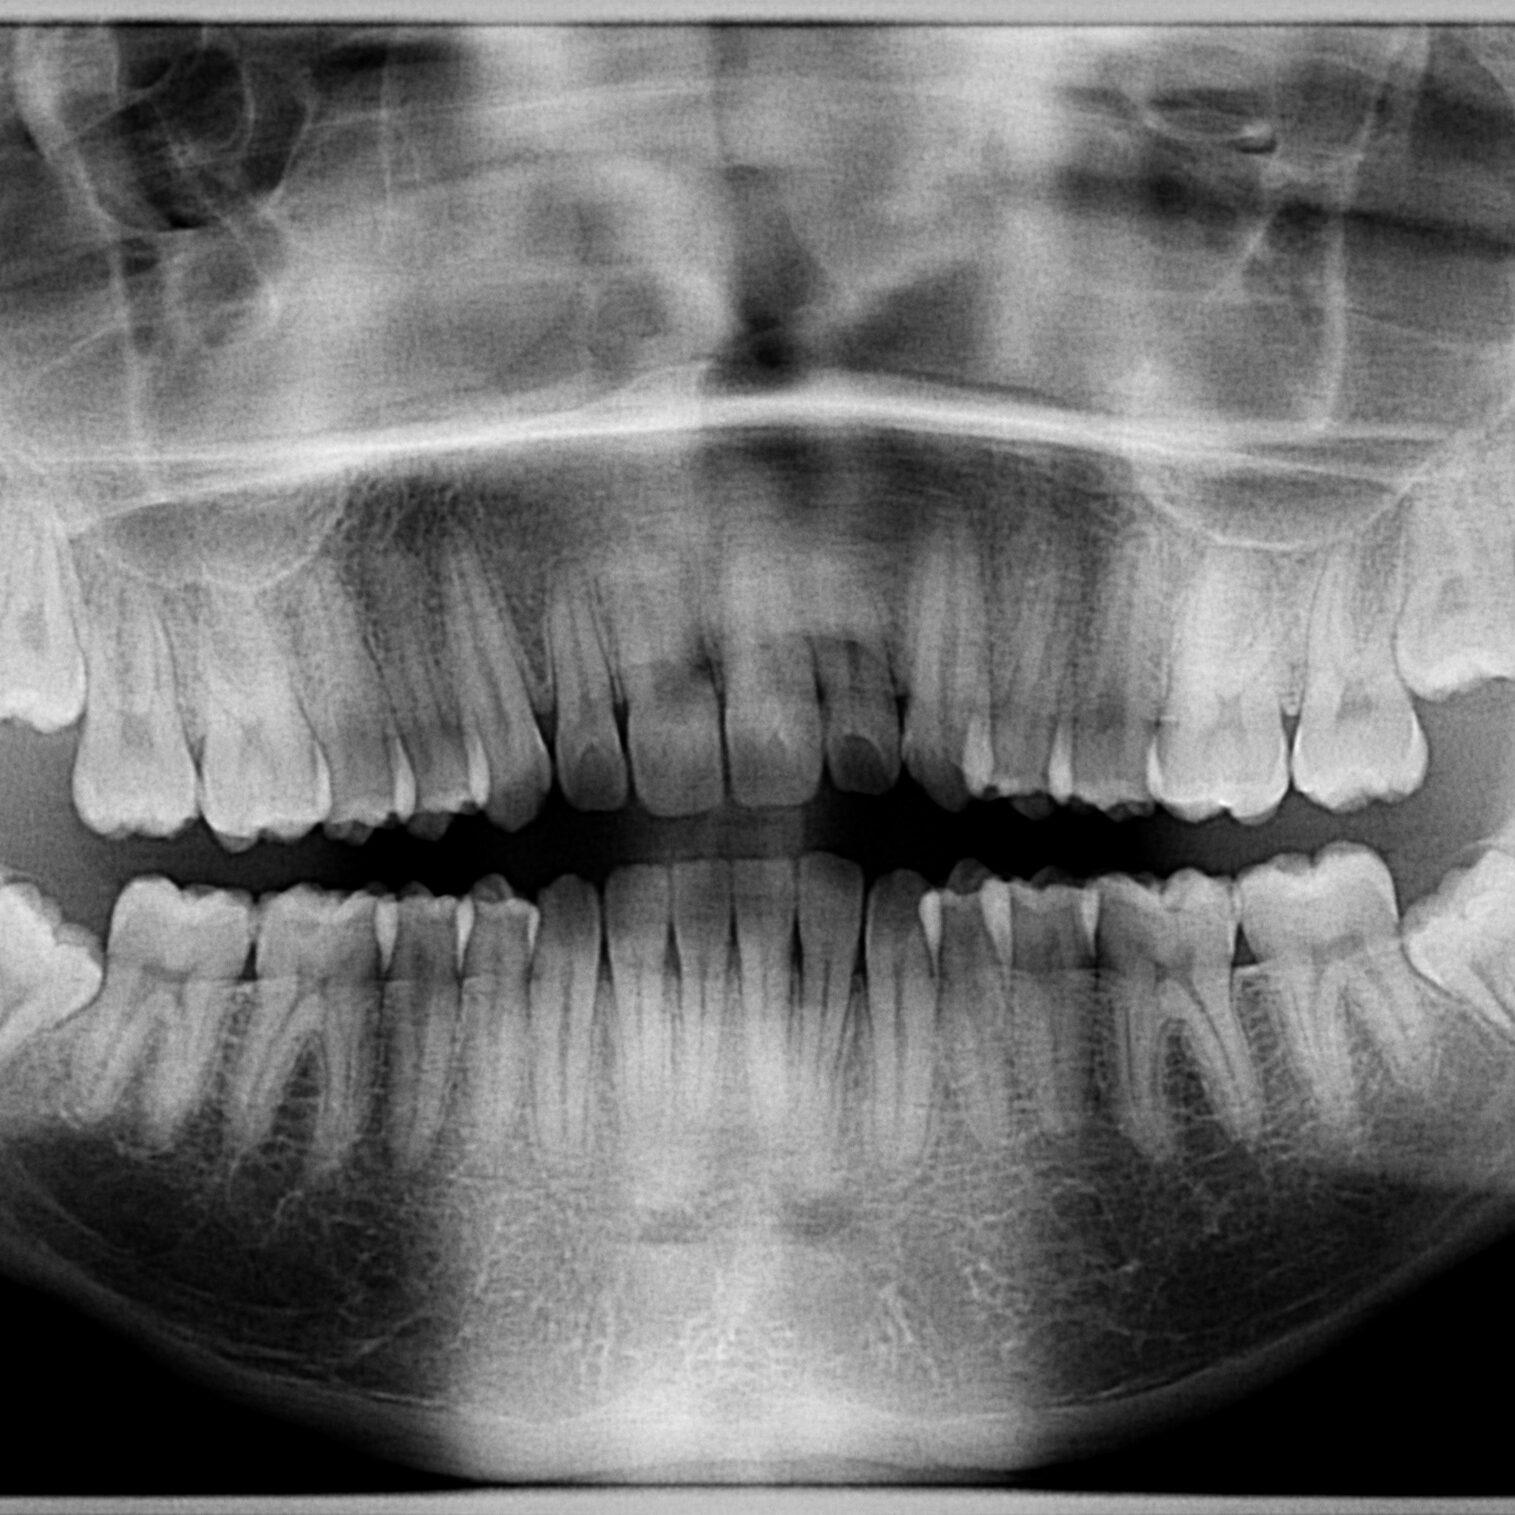

Orthopantomogram

X-ray panoramic two-dimensional image of the jaw that enables quick and easy diagnosis of almost all dental problems.

In addition to the classic orthopantomogram, a bitewing scan and scans of the maxillary sinuses and temporomandibular joint are also available.